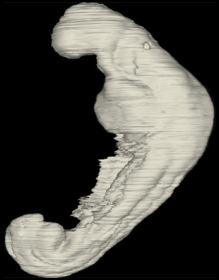

Carnegie Embryo #8943 | Location: 05-03-01

Keywords: amnion, amniotic cavity, dermatomyotome 6 (C-2), dorsal aorta, hepatic antrum, junction of left horn of sinus venosus and left umbilical vein, left umbilical vein, midgut, pericardial cavity, peritoneal cavity, postcardinal vein, right horn of sinus venosus, umbilical vesicle wall, ventral body wall

Source: The Virtual Human Embryo.